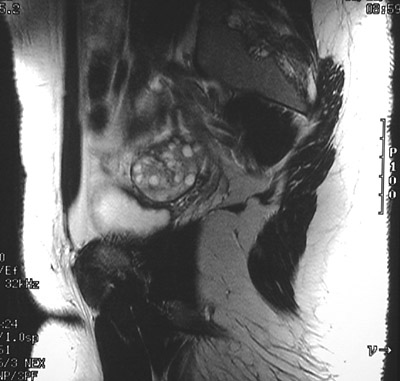

This MRI scan of the pelvis in sagittal view demonstrates multiple small peripheral fluid-filled cysts of an enlarged ovary consistent with polycystic ovary.